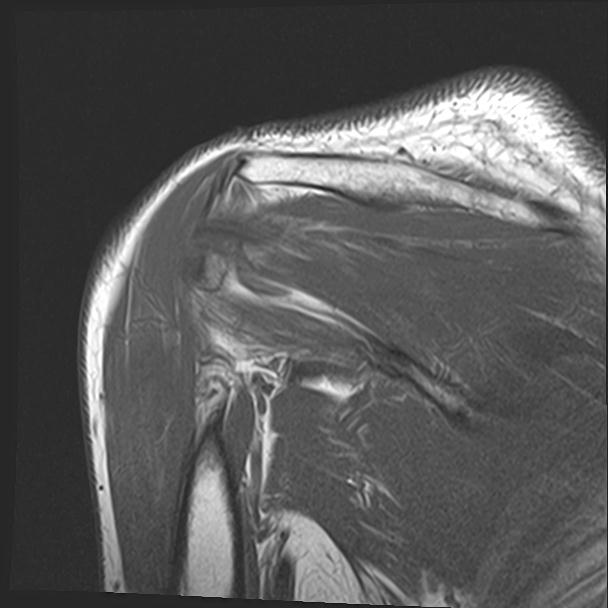

60058 3/9 11/4 右肩 2R+MRI 73歳男性 肩腱板損傷